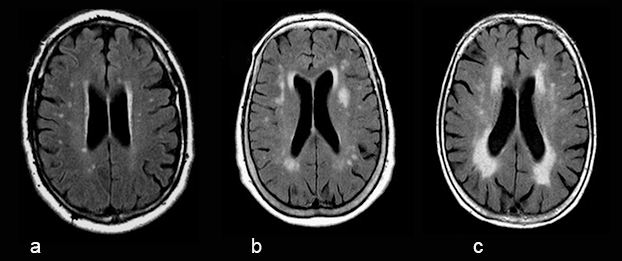

Fazekas-luokitus «Fazekas F, Chawluk JB, Alavi A ym. MR signal abnor...»3 valkean aineen vaskulaarimuutosten luokitteluun

Valkean aineen luokittelussa voidaan käyttää modifioitua Fazekasin neliportaista luokittelua «Fazekas F, Chawluk JB, Alavi A ym. MR signal abnor...»3, jossa Gr 0 on normaali, ei muutoksia, Gr 1 (a) vastaa yksittäisiä syvän valkean aineen < 10 mm:n kirkassignaalimuutoksia ja periventrikulaarista ohutta reunusta, Gr 2 (b) vastaa läiskäisiä 10–20 mm:n kirkassignaalimuutoksia ja periventrikulaarisesti paksua reunusta ja Gr 3 (c) vastaa konfluoivia muutoksia ja epäsäännöllistä paksua reunusta. Muutokset näkyvät parhaiten Flair-sekvenssissä. Tässä kuvasarjassa havainnollistetaan luokittelua vertaamalla rinnakkain kolmen eri potilaan Flair-kuvaa lateraaliventrikkelin korpusosan tasolta.